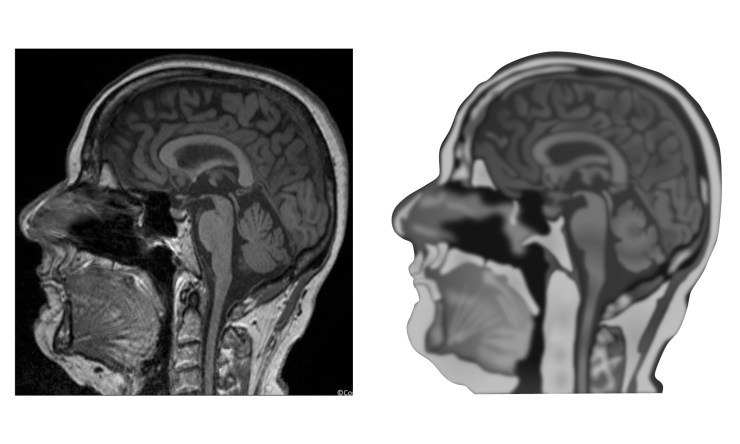

Drawing a realistic illustration of an MRI scan is not a simple process and certainly the image of a sagittal section through a human head would take a lot more work to make it as detailed as the original scan. As shown below, with the drawing to the right of the original MRI scan, the drawing is not particularly convincing.